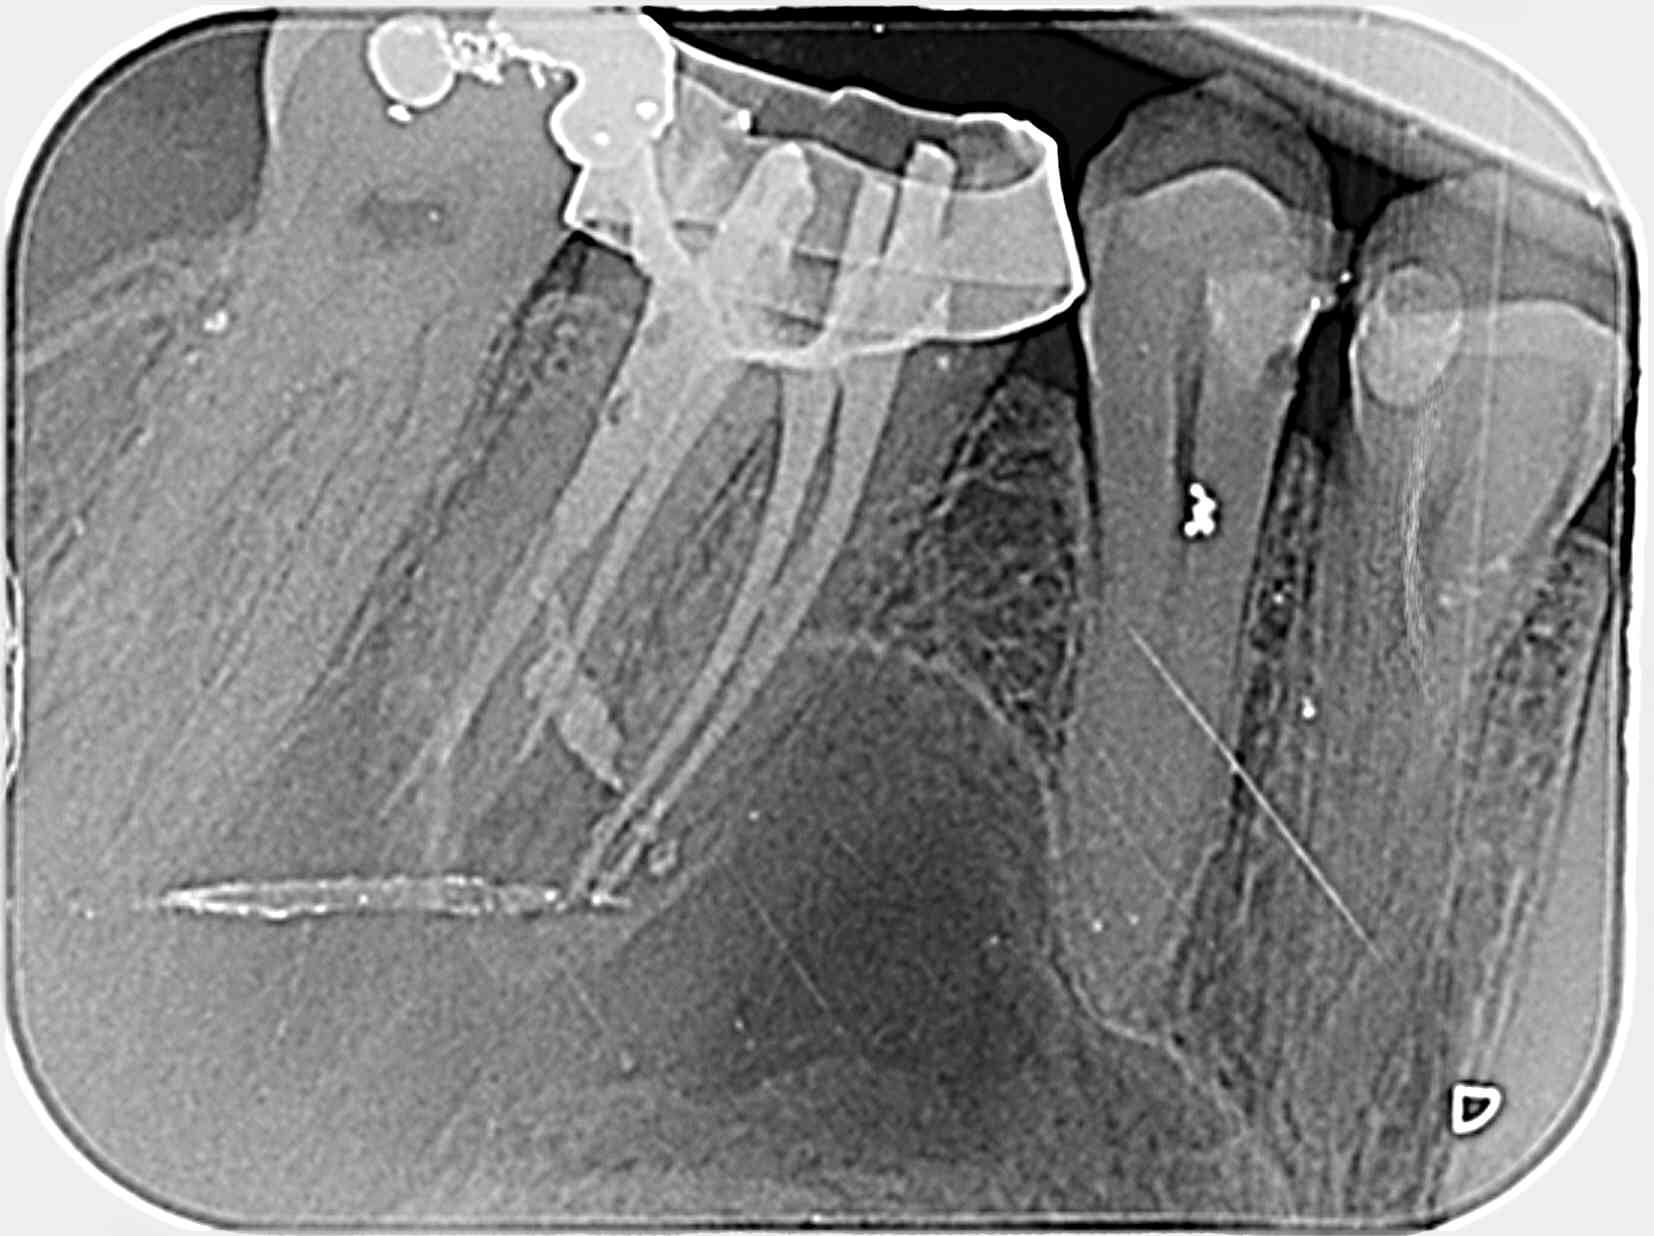

Par curiosité, vous en pensez quoi de la 36? La retro est mal cadrée, mais on voit ce qu'il y a à voir.

36 rpxsaf - Eugenol

On dirait un reliquat de tenon fibré dans la racine dl.

En mesial, région apicale il y a plein de différences de densités (?)

Derrière toute image, il y a une histoire.

La pré op, 5 ans plus tôt. Les lésions importantes laissent souvent une cicatrice.

(et pour savoir ce que j'ai laissé dans la mésiale, je ne m'en rappelle absolument pas; je parierai bien sur un mc spadden)

36 qdat1f - Eugenol